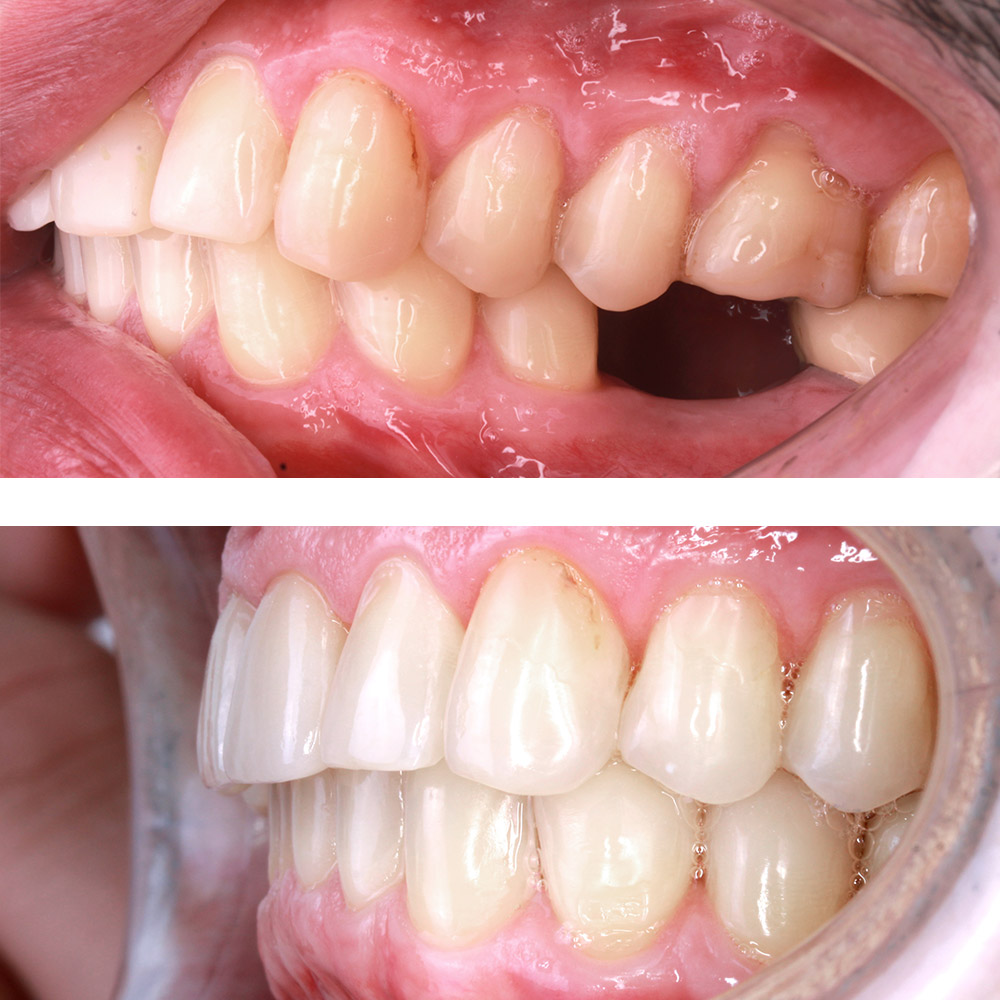

Кейс 12

Бирковская Екатерина Александровна

Количество кап ВЧ 24

Количество кап НЧ 41

ДО

ПОСЛЕ